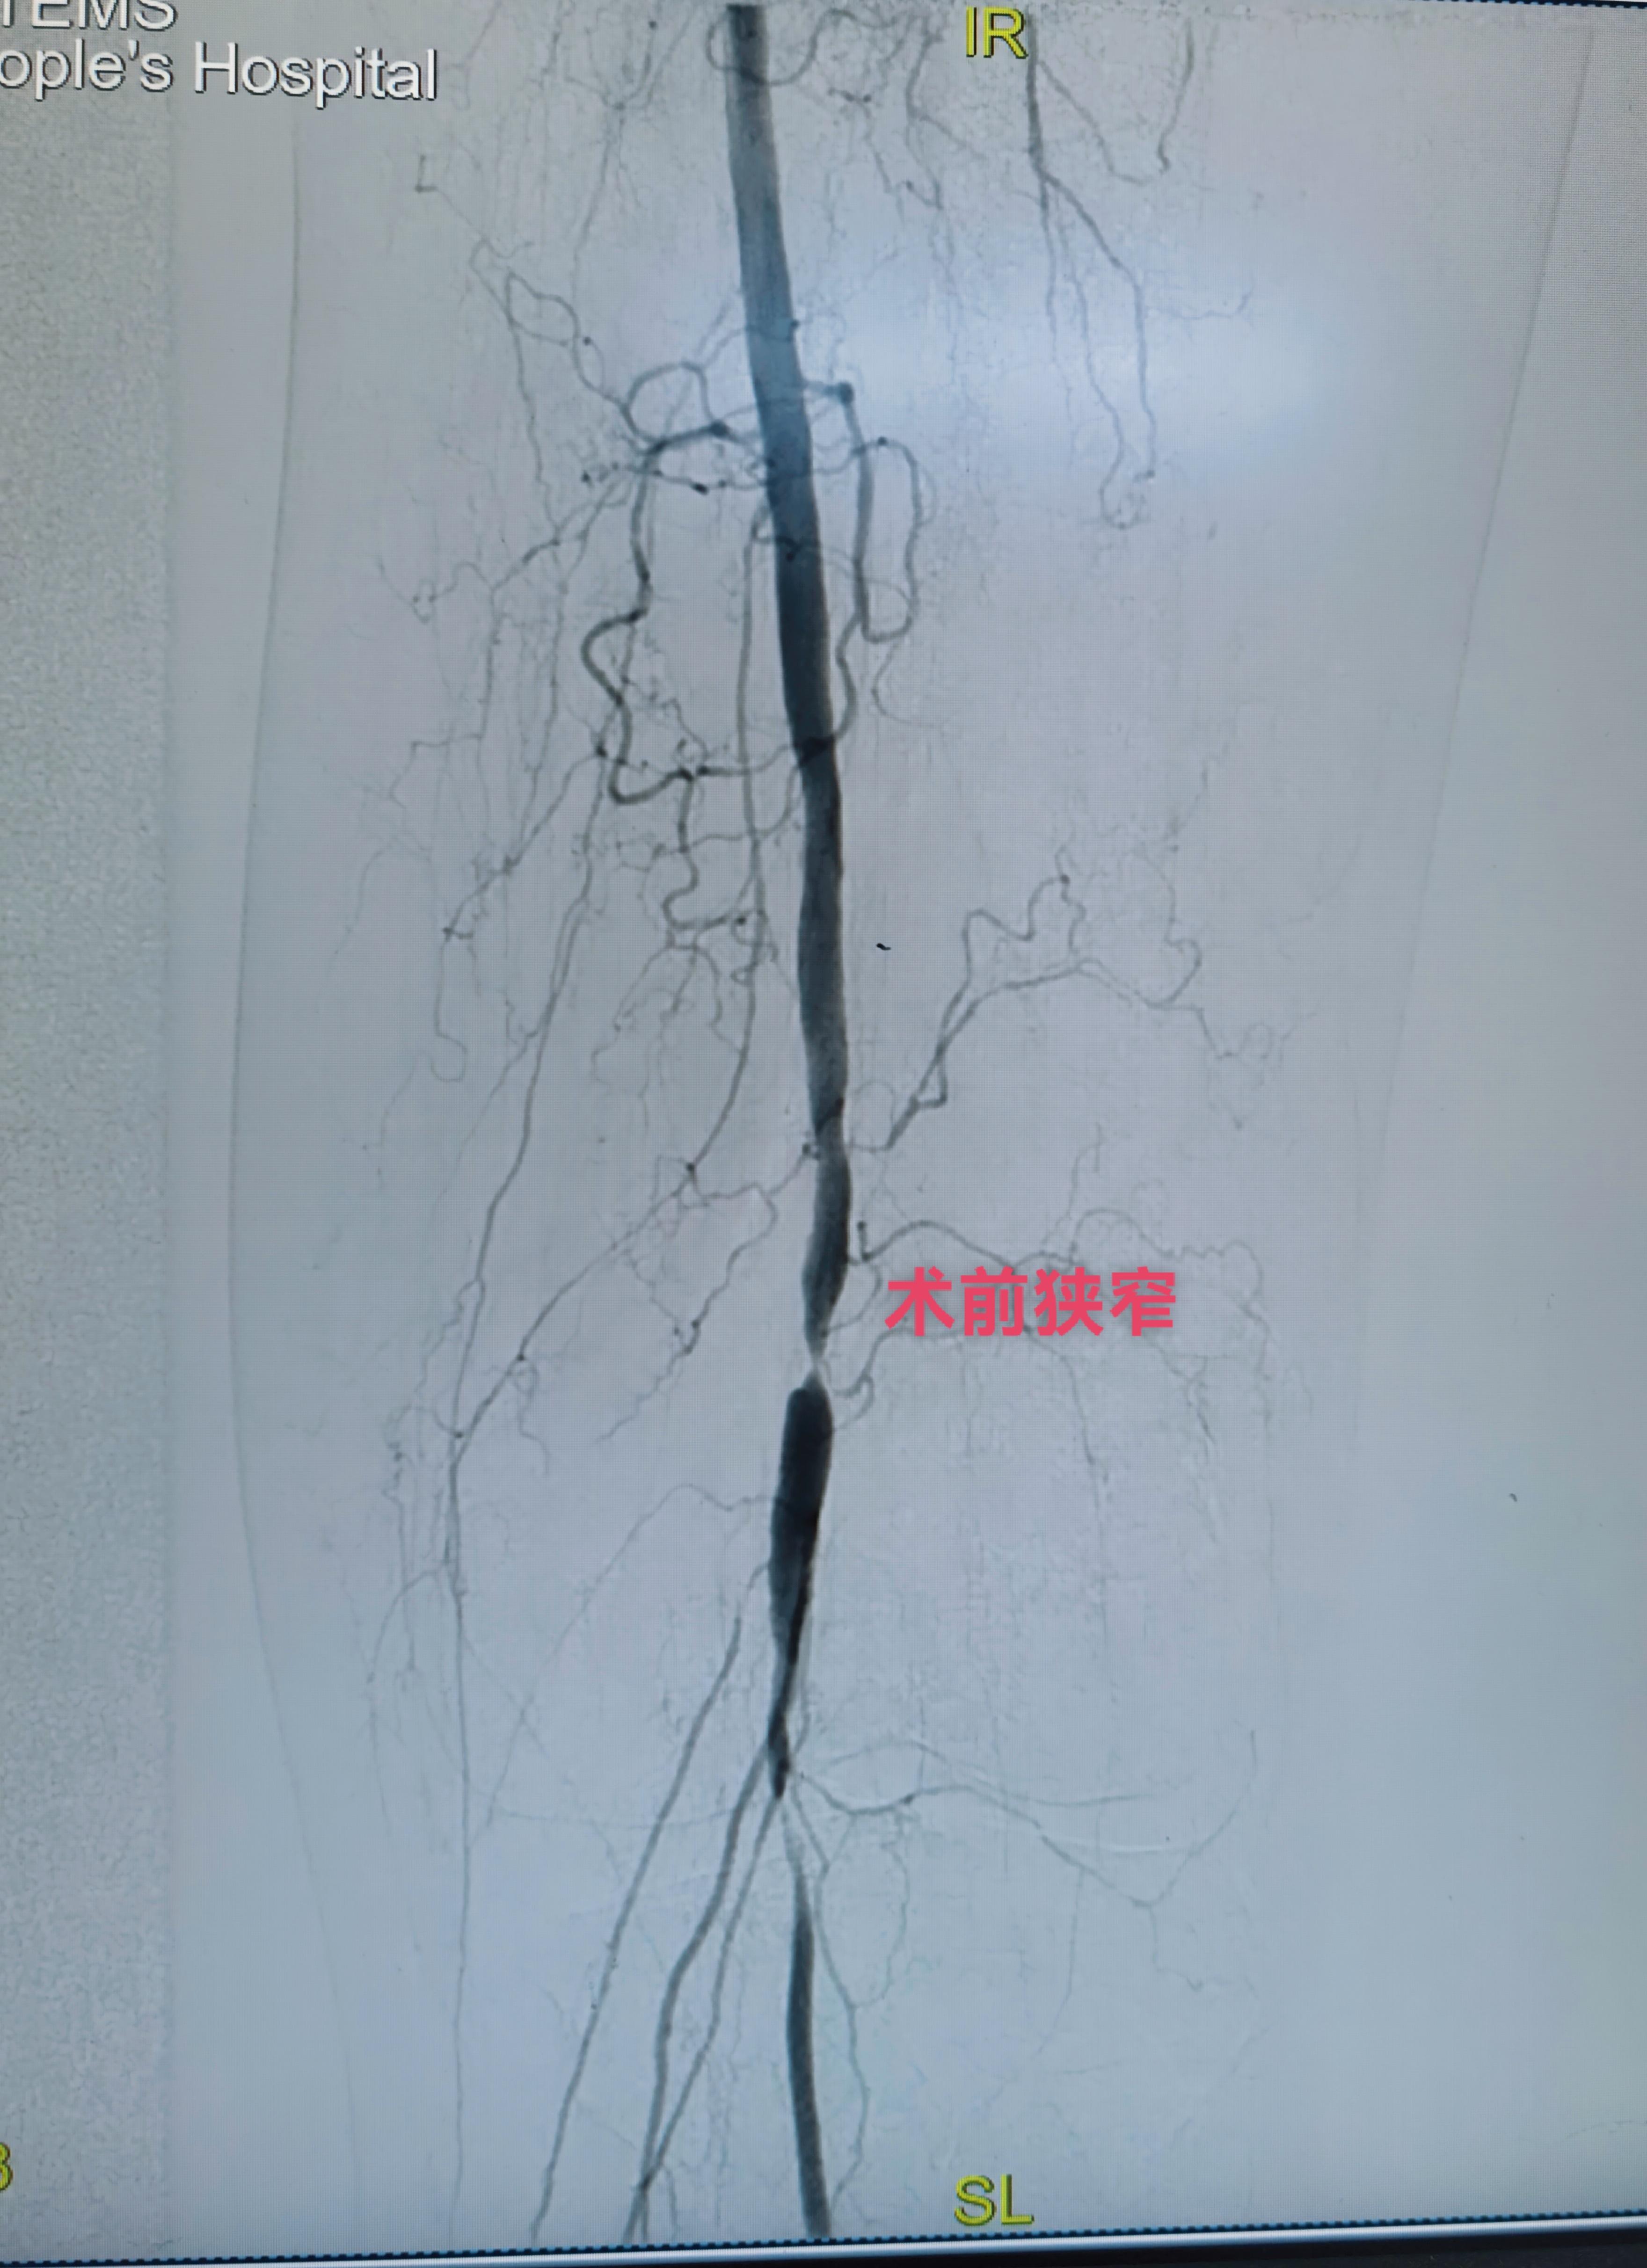

一例糖尿病足,左下肢溃烂不愈合,静息痛严重影响生活。开通闭塞段,行球囊扩张!即刻恢复血流,足背红润皮温升高,疼痛消失!